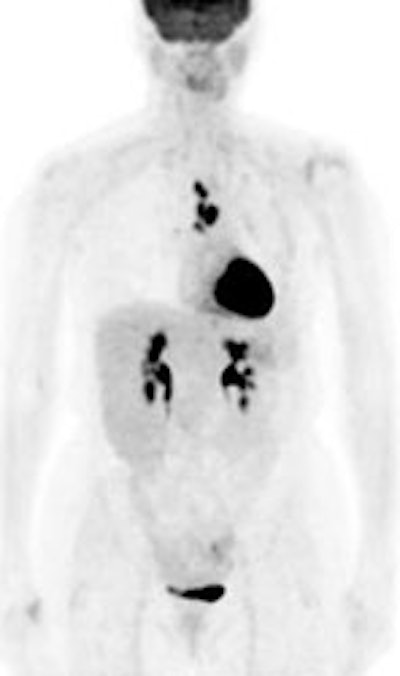

The presence of distant metastases

is classified as stage IV disease and generally precludes a

patient from curative surgical resection [167]. 18FDG

PET has significant potential to be used for detecting

extrathoracic metastases when whole body images are performed

[4,79,80,83,120]. Detection of unsuspected extra-thoracic spread

can be identified in 6% to 24% of patients (mean frequency of

about 13% [167]) and can significantly alter patient management

[80,106,120,133,140,141,143,144,151]. A 2013 meta-analysis demonstrated

a pooled sensitivity of 77% and specificity of 95% for the

detection of metastatic disease [215].

|

Change in stage: The patient below was felt to have Stage IIIB disease based upon the chest CT findings. FDG PET imaging confirmed ipsi- and contralateral mediastinal adenopathy, but also reveal a left scapular metastasis (seen retrospectively on the CT scan [white arrow]). A left iliac metastasis was also identified (black arrow right PET image). This resulted in a change in patient stage as the patient was now has Stage IV disease. |